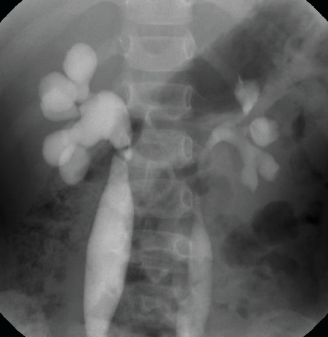

Febrile urinary tract infections (UTIs) are common in children, and an initial UTI predisposes them to additional UTIs, especially in the presence of an anatomic urinary system problem.

An 11-year-old obese girl presented to the orthopedic clinic with a history of bilateral knee pain. The girl had visited an urgent care clinic 8 months prior for left knee pain.